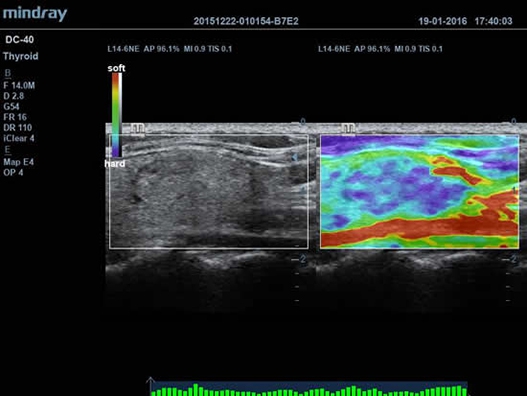

Mindray DC-40 - передовая УЗ-станция с выдающимися возможностями в области медицинской диагностики. Компания Mindray разработала это устройство с учетом высоких требований врачей к качеству изображения и быстродействию. DC-40 обеспечивает высокое качество изображения и точность диагностики, что является необходимым в повседневной практике врачей. Технологии, применяемые в этом устройстве, позволяют получать четкое и детализированное изображение.

Технологии iBeam, iClear и iScape, применяемые в DC-40, позволяют получать объемные изображения высокого качества без помех и зернистости в зоне сигнала. Панорамная визуализация с расширенным обзором анатомических структур решает проблемы сложных диагнозов, которые ранее создавали значительные трудности в ультразвуковой диагностике.

• Функция эластографии Natural Touch позволяет проводить эластографические исследования.

Natural Touch Elastography:

Да